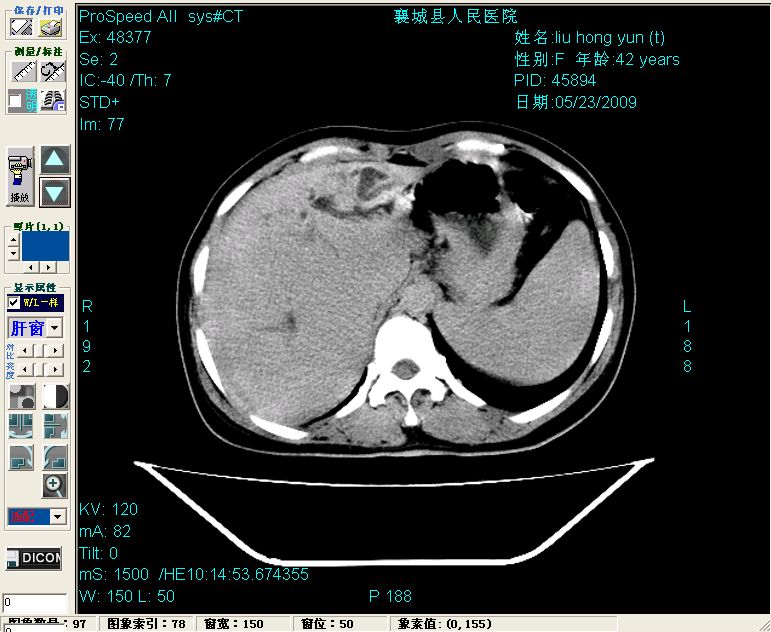

增强:

增强动脉期前述低密度区轻度早其强化,门脉期强化程度显著增高,延期扫描强化程度下降,但仍为相对高密度影

胰头部见结节状高密度影,其前方略可分辨扩强胆部管,平扫到增强始终有,但现在尚难与胃肠造影剂鉴别.

结合病史考虑,1现在引起黄疸体征的原因应该是胆总管胰段结石阻塞,建议局部胃肠造影剂排空后复查.

2左肝及右肝前叶表现考虑胆囊摘除术后所致的肝动门脉瘘形成,慢性纤维组织炎性增生.不完全除外左肝胆管细胞癌

3脾大,可能与动门脉瘘所致门脉高压有关